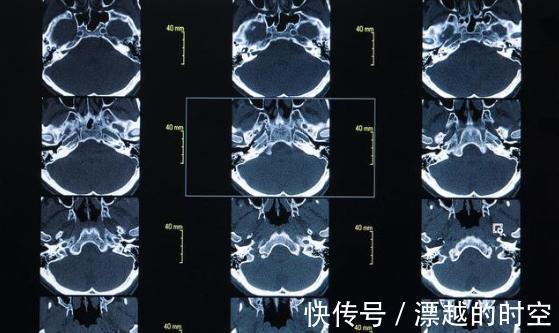

医生立即对男孩进行体征检查,判断可能是脑部血管出现了问题,同时抽血检查血液。医生申请急诊绿色通道进行脑部CT检查,发现大脑内一血管已严重堵塞。